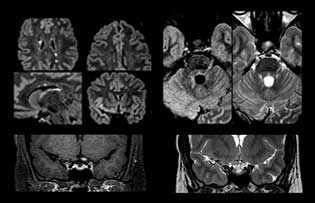

Dr. Savatovsky uses five or six different ExamCards for imaging a mass or a known tumor in the brain. “If there is a mass in the brain we try to characterize it to inform the neurologist for determining next steps or to help neurosurgeon prepare for a surgery or biopsy. For follow-up after treatment we have different protocols for different treatments and we adapt for intra- or extra-axial tumors.” “That is the most comprehensive exam we would do. Ingenia has the good spatial resolution and high SNR to provide all this information, and the flexibility to use shorter sequences, so we can do a very comprehensive examination in a limited time.”

“The biggest challenges are properly characterizing the lesion and giving the surgeon all the information needed, such as the location of vessels and functional areas. Sometimes a very comprehensive exam is necessary, such as when a mass has been discovered at another hospital after which the patient is referred to us. We then do both lesion characterization and preoperative imaging in one exam, so both morphologic and functional assessment. For morphologic assessment we will use pre- and post-contrast T1-weighted imaging, FLAIR to assess infiltration, and diffusion. For functional characterization we will perform perfusion, spectroscopy, and susceptibility weighted imaging to look for micro vessels or micro hemorrhage inside the lesion[4]. For preoperative imaging we perform specific morphologic imaging that is compatible with the navigation system; depending on the location of the tumor, we would do fMRI or DTI.”